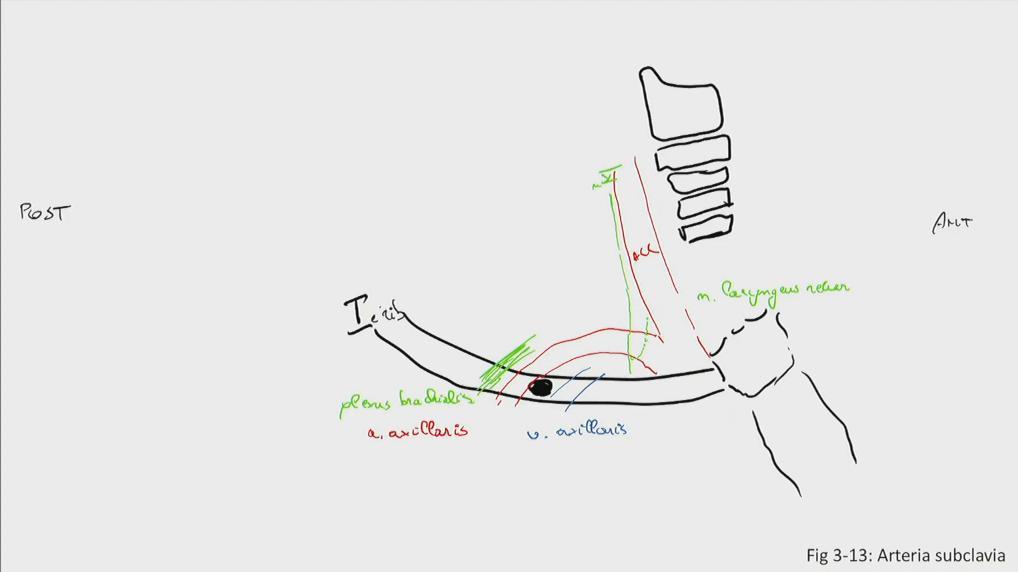

Fig 3.13: a. subclavia

|

|